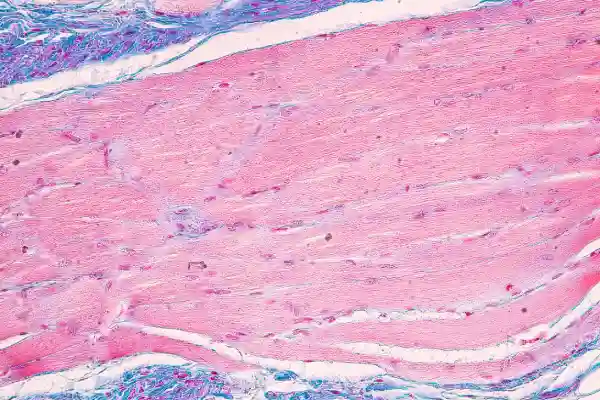

Tay-Sachs Disease

The availability of jscreen is a promising step in building upon the initial success of Tay-Sachs screening. Traditionally, Tay Sachs carrier screening required blood enzyme testing, but today’s sequencing method allows highly accurate testing to be performed on saliva. (In a small percentage of cases, blood enzyme testing will be needed in addition to saliva testing. A JScreen genetic counselor will notify you if that is the case, and help you arrange to have this performed.)